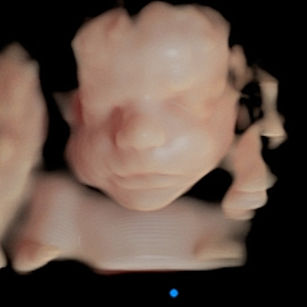

Look at these beautiful face pictures, even with an Anterior Placenta!

26 Weeks 5 Days Pregnant